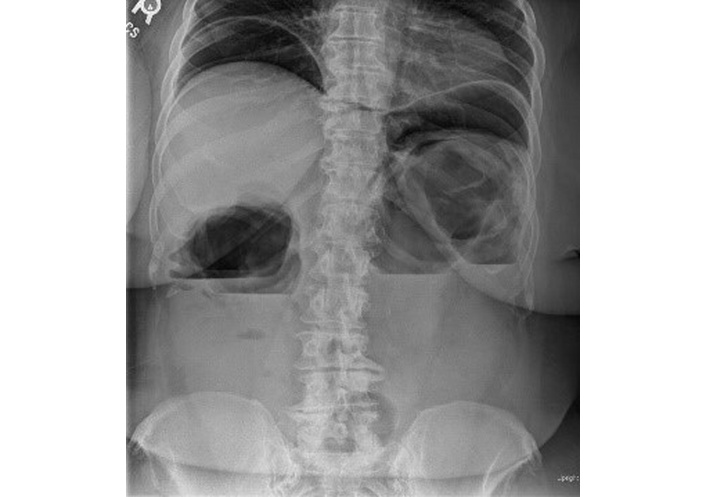

An initial loading dose of IV infliximab 10 mg/kg was administered without any immediate issues. Later that evening, while ambulating to the restroom, the patient experienced severe left upper quadrant pain radiating to the left arm, accompanied by shortness of breath. A STAT abdominal radiograph showed significant intraperitoneal free air and marked colonic dilation with large air-fluid levels (Figure 3). She was immediately started on broad-spectrum antibiotics (IV piperacillin-tazobactam 3.375 g every 6 hours) and taken emergently to the operating room. Exploratory laparotomy revealed gross perforations at the splenic flexure, transverse colon, and ascending colon near the cecum, with pronounced inflammation in the left colon. An extended right hemicolectomy with end ileostomy was performed. Pathologic evaluation of the resected specimen showed severe acute colitis with ulceration, submucosal and subserosal abscesses, transmural inflammation, and non-caseating granuloma formation characterized by the presence of epithelioid cells, multinucleated giant cells, and lymphocytes, without necrosis (Figure 4).

Upright abdominal radiograph demonstrating significant intraperitoneal free air, marked colonic dilation, and large air-fluid levels, consistent with bowel perforation.